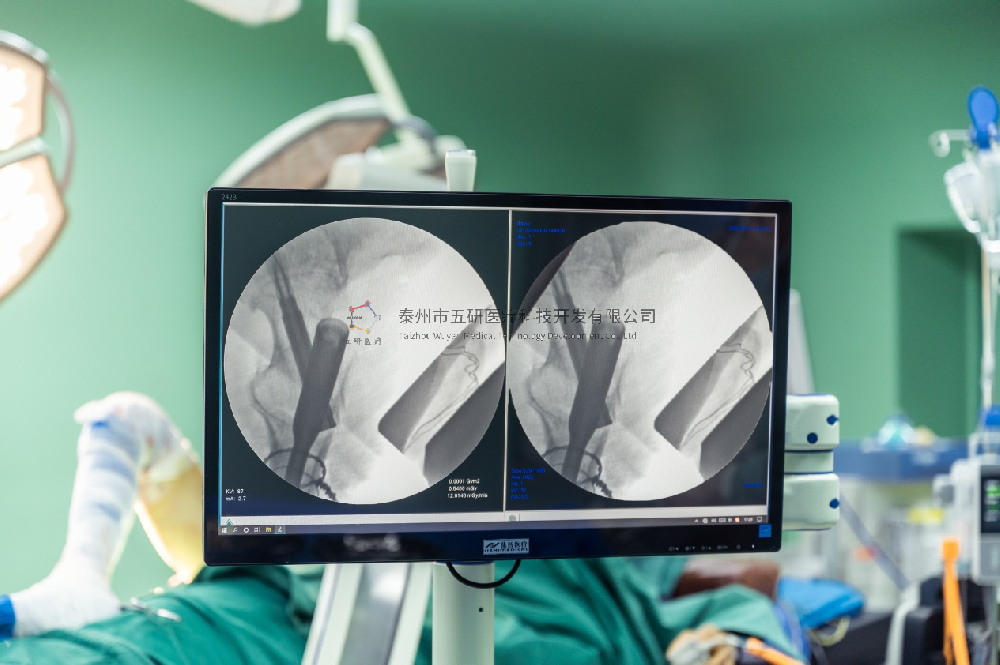

術(shù)中圖: